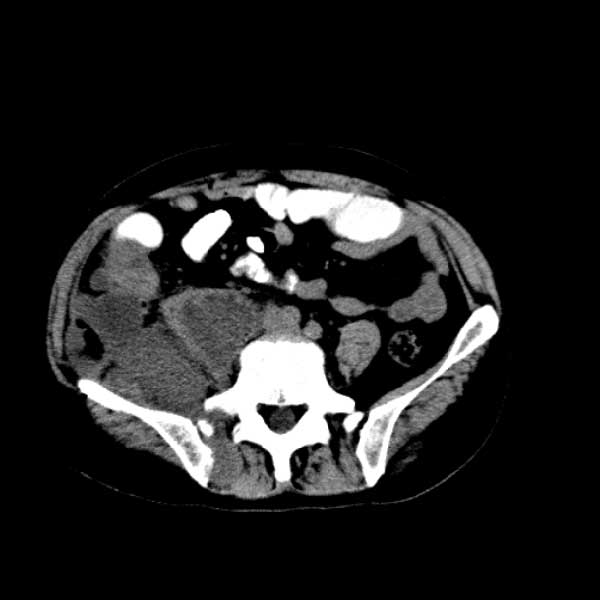

标题: CT13513:男 71 腹部疼痛20余天,近几天高热就诊,骨窗未见异 [打印本页]

标题: CT13513:男 71 腹部疼痛20余天,近几天高热就诊,骨窗未见异

考虑感染性病变可能性大,起源于阑尾?

感染,脓肿形成

考虑为化脓性阑尾炎.脓肿形成.及多肌肉累及.

考虑右侧腰大肌脓肿,向右髂窝、右腹股沟流注。

支持化脓性阑尾炎伴右髂窝脓肿、腰大肌腰方肌脓肿形成。

考虑腹腔及盆腔化脓性炎症,累及右侧髋关节及腹股沟区.

首先考虑化脓性阑尾炎伴腰大肌、腰方肌脓肿,不除外回盲部结核。

回盲部癌待排除。

患者肠镜检查考虑结肠癌,病理证实

患者肠镜检查考虑结肠癌,病理证实。肺部ct可见多发结节,考虑转移